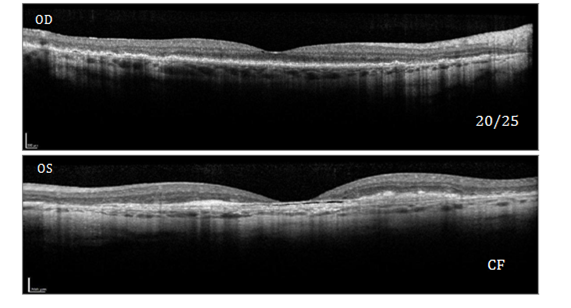

Visual acuity was measured 20/25 in the right eye and count-fingers at 5 feet in the left eye with symmetrically reactive pupils and normal intraocular pressures. Retinal examination revealed well-circumscribed scalloped areas of atrophy in both eyes (Figure 1), particularly in the outer retinal and choroidal areas. The presence of a central fibrotic CNVM was also seen in the left eye. Spectral Domain OCT showed outer retinal atrophy and subretinal fibrosis with the left eye (Figure 2) to a greater degree than the right eye. Baseline diagnostic imaging was obtained to document the pathological course. Given the presence of sub-RPE deposits noted in the retina along with discerned areas of RPE loss and choroidal atrophy in the macula and periphery, the diagnosis of L-ORD was made for both eyes.

Figure 2 Optical coherence tomography of right eye and left eye confirming sub RPE deposits OU, outer retinal atrophy OU and sub retinal fibrosis OS.